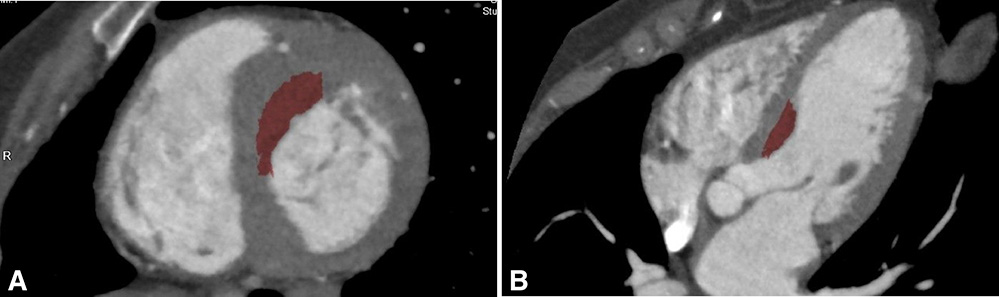

Area of planned myectomy (red) is visualized on the (A) short axis and (B) long-axis views of left ventricle/right ventricle on gated CT.

While septal myectomy is the preferred treatment for patients with obstructive hypertrophic cardiomyopathy refractory to medical therapy — and routinely performed at NewYork-Presbyterian as the least-invasive surgical approach — it is a challenging procedure that relies on a surgeon’s subjective assessment through a limited transaortic surgical view. The mainstay of preoperative imaging assessment remains transthoracic echocardiography, though this modality can significantly mislead in preoperative assessment with regards to location and severity of left ventricle thickness. To address this, Columbia and Weill Cornell cardiologists and cardiac surgeons have developed a virtual myectomy (VM) technique using 3-dimensional reconstruction of gated cardiac CT to assist the intraoperative objective assessment of the adequacy of the resection.

Using gated cardiac CT with 3D reconstruction, they were able to reproduce the appearance of the heart under cardioplegia in diastolic arrest; 100 percent of relevant surgical landmarks in all patients were seen preoperatively. Postoperative discussions indicated that preoperative virtual myectomy was helpful in determining how much myocardium to resect as well as clarifying surgical landmarks and anatomy during septal myectomy. Other benefits included detailing the regional difference of septal thickness and width of the “septal band.” The Weill Cornell and Columbia physicians believe this also contributed to achieving a satisfactory clinical outcome.